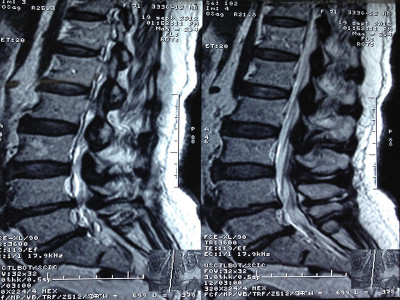

.

Casos Neuroloquirúrgicos

Envíado por Dr. Ruben Eduardo Amaya Contreras